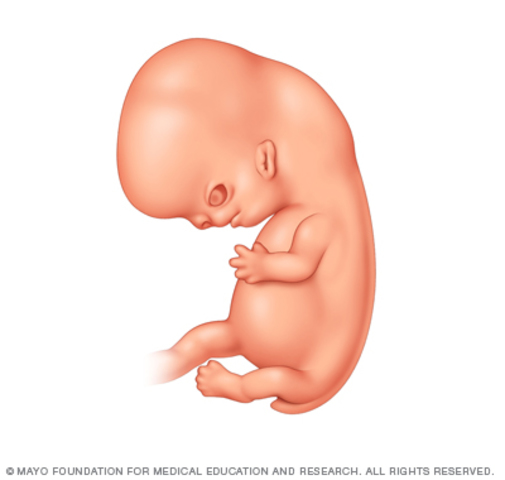

• Week 6

Week 6

Muscles form, bent neck, webbed hands and feet, segmented back

• Week 7

Week 7

Fingers and toes separate, eyes and ears formed